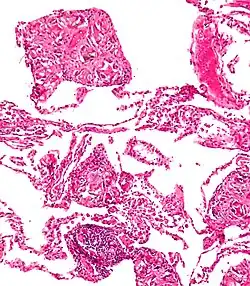

Talcosis

La Talcosis es una enfermedad pulmonar causada por la inhalación de talco.

Se ha relacionado con silicosis resultante de la inhalación de talco y silicatos. También está ligado al consumo de heroína donde podría ser usado el talco utilizado como un adulterante para aumentar el peso en las ventas de calle, por lo que la inyección de heroína con talco diluido causa talcosis ..."[1]

La talcosis también puede surgir de la inyección de medicamentos destinados a la administración oral, como el talco está presente en muchas tabletas y cápsulas que son objeto de abuso por vía intravenosa , tales como benzodiazepinas , dextroanfetamina , y en la prescripción de narcóticos. It is one of several noted associations and possible risks of street heroin use.[2]